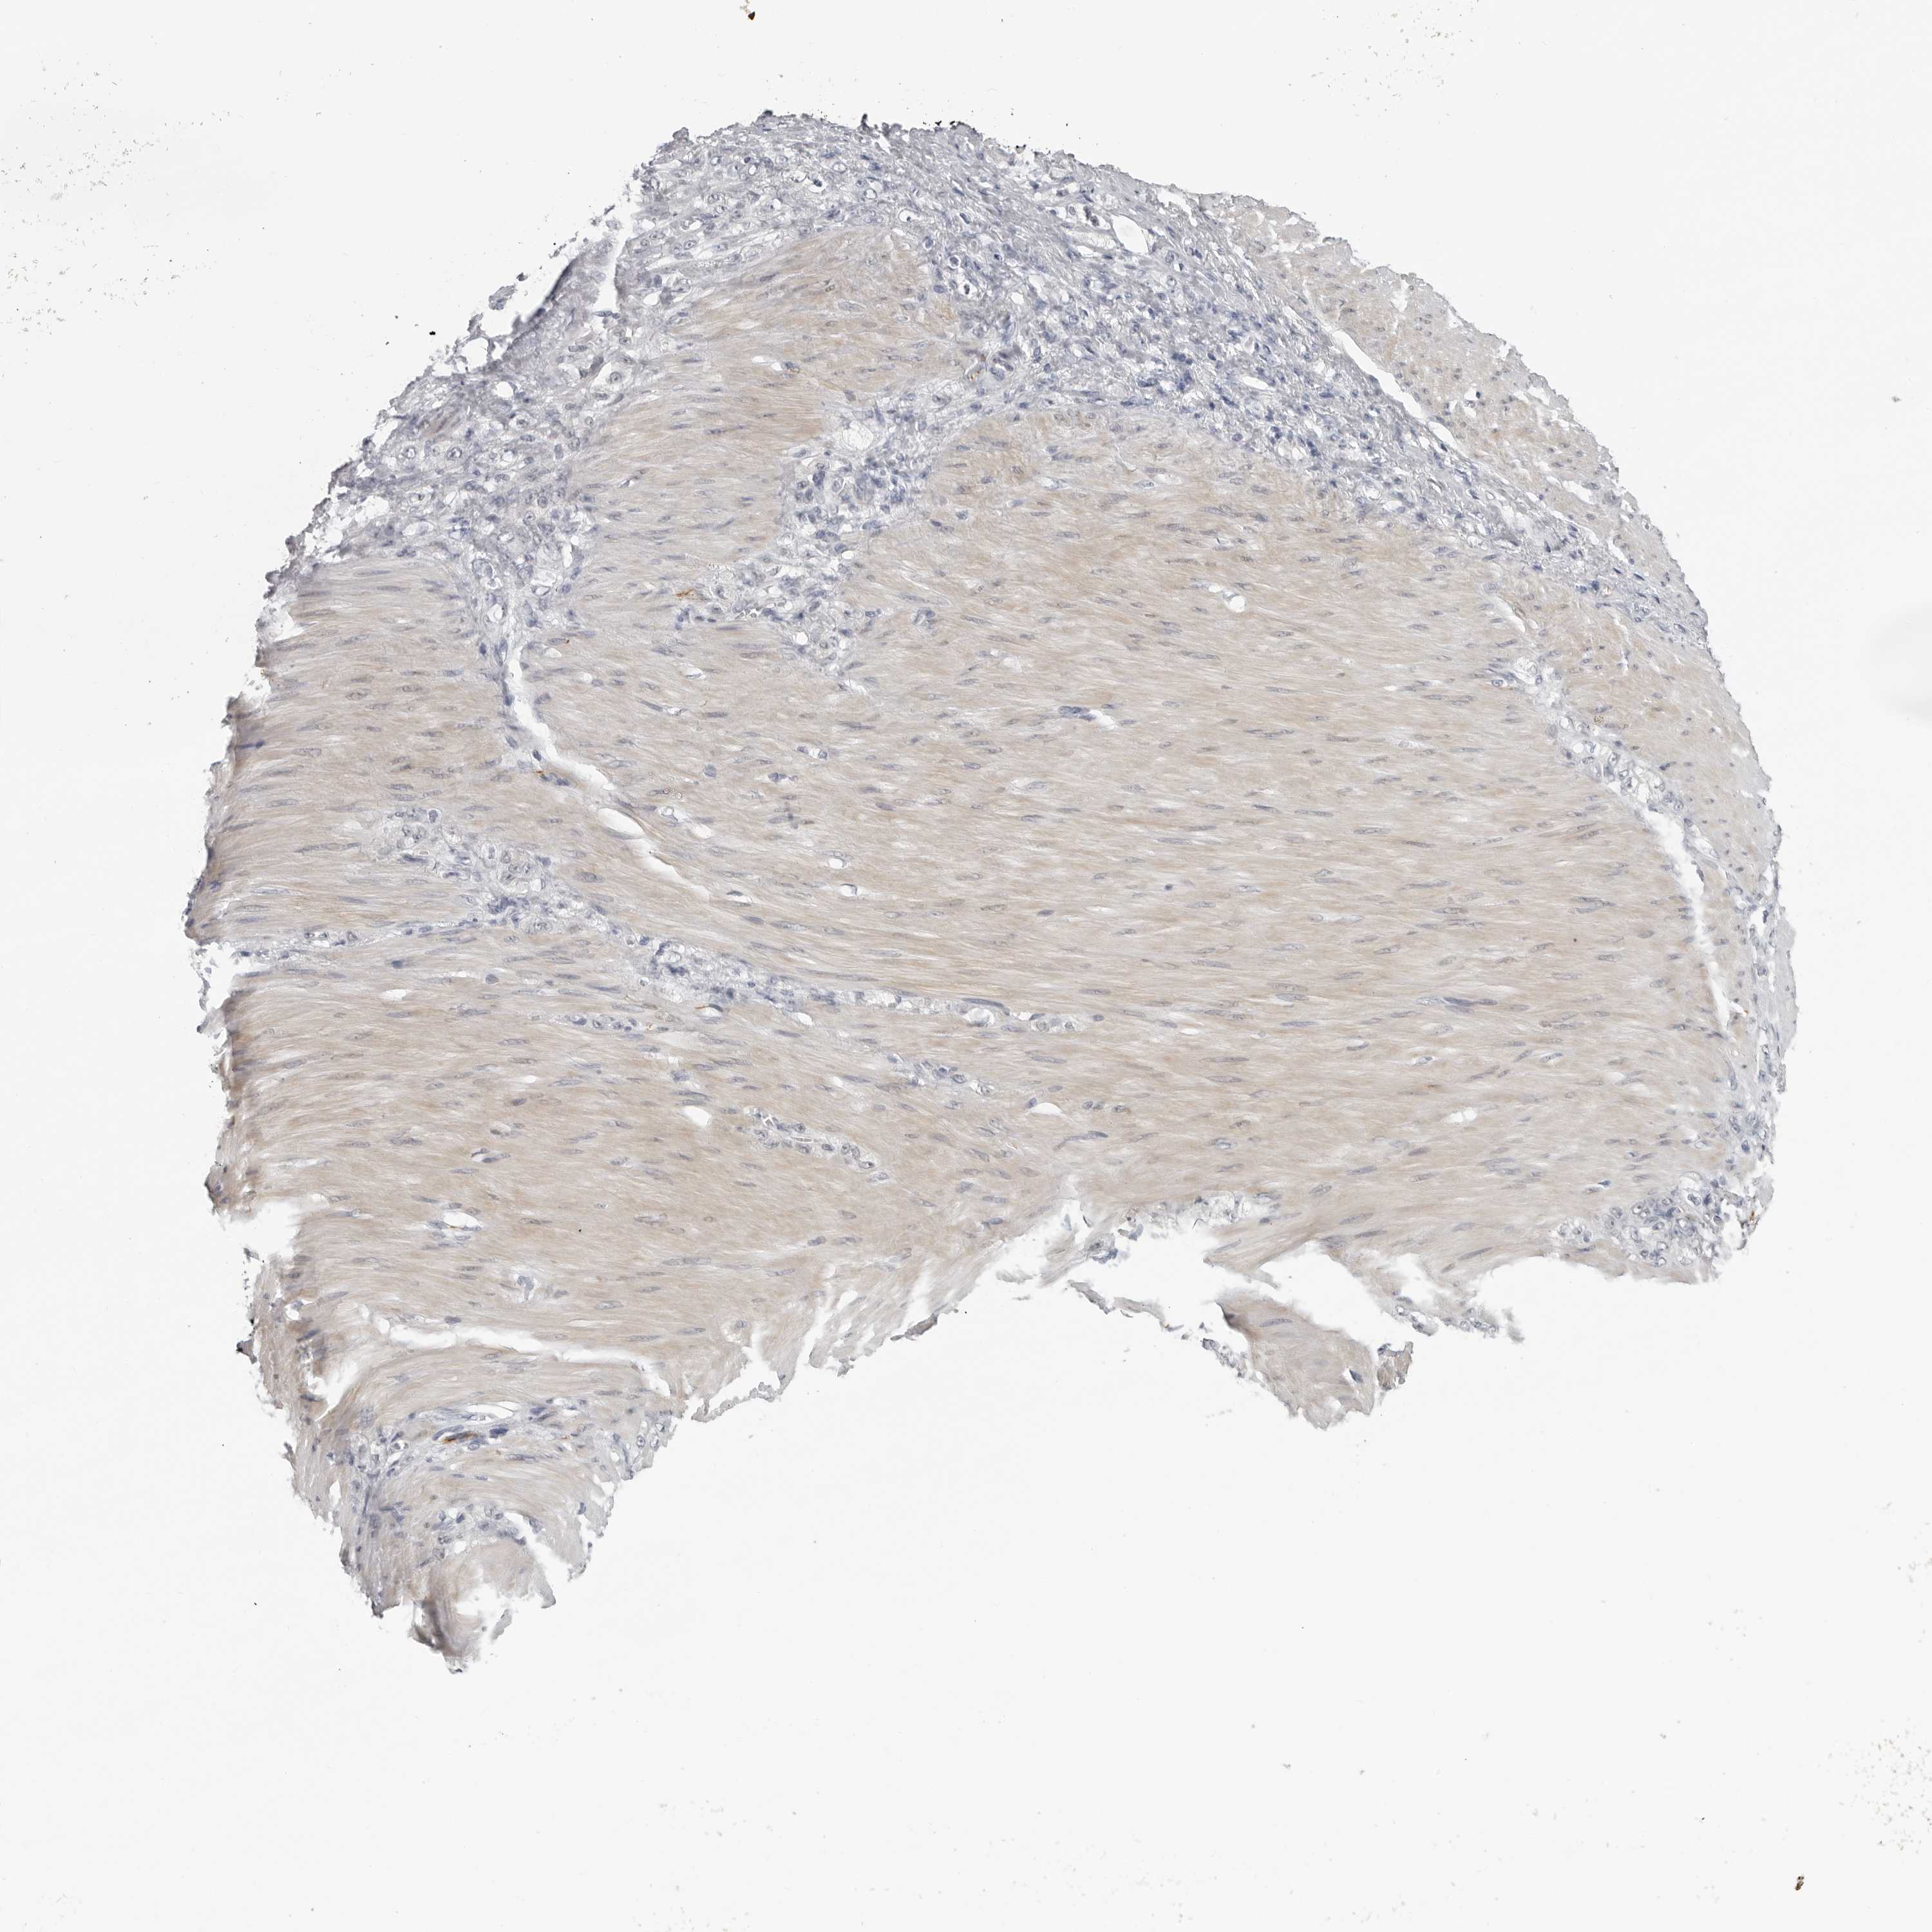

STOMACH CANCER - Protein expressioni

A mouse-over function shows sample information and annotation data. Click on an image to view it in a full screen mode. Samples can be filtered based on level of antibody staining by selecting one or several of the following categories: high, medium, low and not detected. The assay and annotation is described here.

Note that samples used for immunohistochemistry by the Human Protein Atlas do not correspond to samples in the TCGA dataset.

Antibody stainingi

Antibody staining in the annotated cell types in the current human tissue is reported as not detected, low, medium, or high, based on conventional immunohistochemistry profiling in selected tissues. This score is based on the combination of the staining intensity and fraction of stained cells.

Each image is clickable and will lead to virtual microscopy that enables deeper exploration of all samples and also displays staining intensity scores, fraction scores and subcellular localization as well as patient and tissue information for each sample.

Antibody HPA026562

Antibody HPA028260

Staining

High

Medium

Low

Not detected

Intensity

Strong

Moderate

Weak

Negative

Quantity

>75%

75%-25%

<25%

None

Location

Nuclear

Cytoplasmic/membranous

Cytoplasmic/membranous,nuclear

Adenocarcinoma, NOS